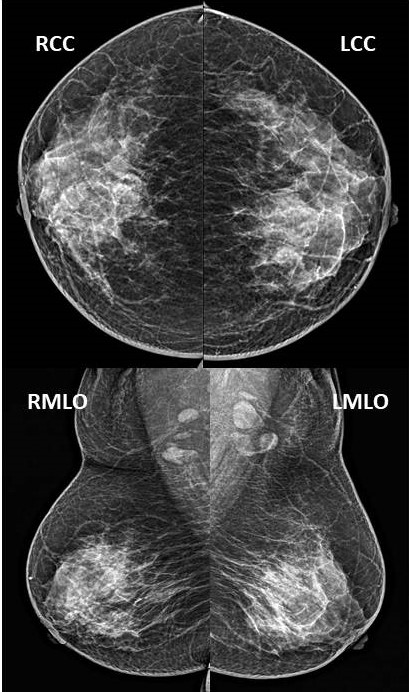

A 45-year-old asymptomatic woman with no family history of breast canc...

Read More